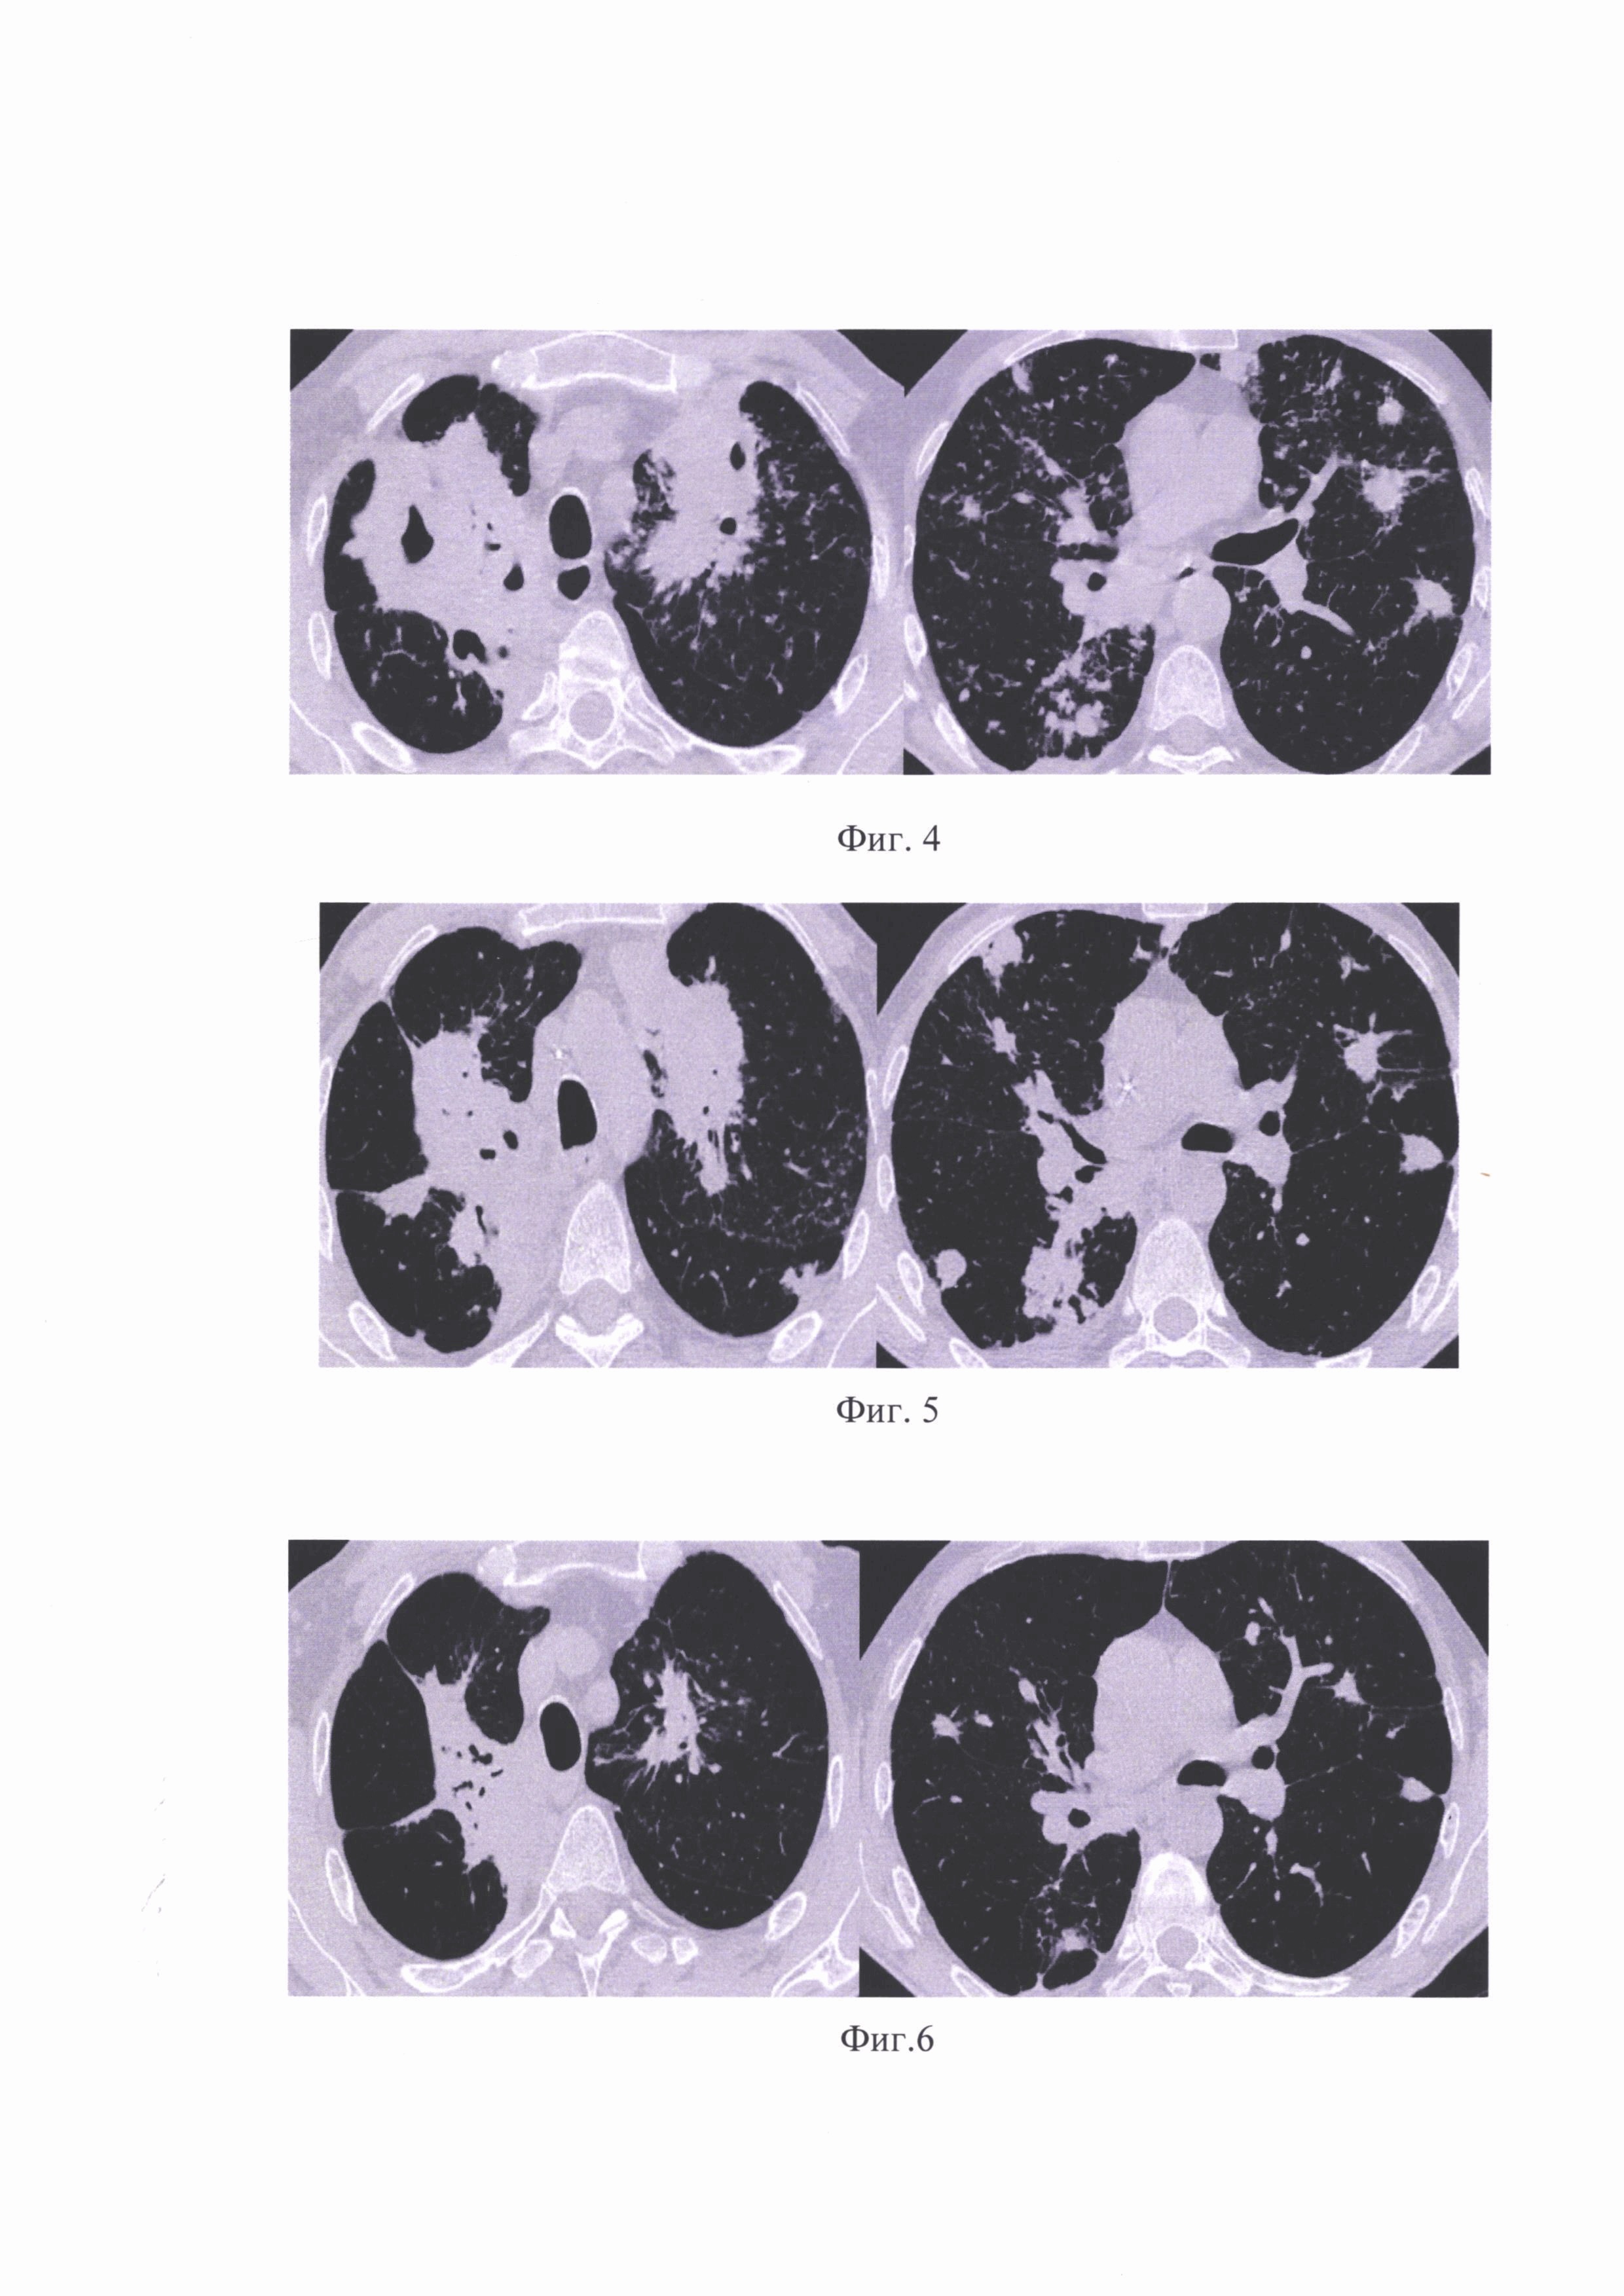

Изобретение относится к медицине, а именно, к фтизиатрии, и может быть пользовано при диагностике гиперреактивности бронхов (БГР) у курящих и некурящих больных туберкулезом, а также ее мониторинга и лечения. Бронхи здорового человека реагируют на различные раздражители. Попадание их в бронхиальное дерево может сопровождаться кашлем, а в некоторых случаях и клиническими проявлениями бронхоспазма (дискомфорт в грудной клетке, удушье). Это является физиологическим защитным механизмом, что предотвращает попадание раздражителей в нижние дыхательные пути. Указанный защитный механизм лежит в основе бронхиальной гиперреактивности. Бронхиальная гиперреактивность - это выраженная реакция бронхов на различные раздражители, приводящая к падению показателей бронхиальной проходимости на 35% и более. При этом у здоровых лиц введение в бронхи тех же концентраций раздражителей, не вызывает значимого снижения бронхиальной проходимости. Несмотря на огромное количество исследований, посвященных бронхиальной гиперреактивности механизмы, лежащие в основе ее развития недостаточно изучены. На ее формирование влияет множество внешних (аллергены, респираторная инфекция, поллютанты, курение, метеоусловия, физическая нагрузка, пища, лекарства, стресс) и внутренних (генетическая предрасположенность, атопия, пол) факторов, приводящих к развитию персистирующего воспаления дыхательных путей, что как известно формирует и усугубляет БГР. В развитии БГР, принимают непосредственное участие иммунная, нервная и эндокринная системы, физиологическая реакция которых на воздействие различных провоцирующих факторов приводит к морфофункциональным изменениям нижних дыхательных путей. Также известно, что бронхи имеют обилие нервных окончаний, отвечающих за их работу. Длительное воспаление бронхиальной стенки приводит к нарушению функции холинергической и адренергической системы. В связи с чем, ранняя диагностика БГР является весьма актуальным. Табакокурение является важным фактором риска развития БГР, которая поддерживается постоянным поступлением компонентов табачного дыма. На этом фоне БГР может прогрессировать и приводить к развитию бронхообструктивных нарушений и в дальнейшем, к формированию хронической обструктивной болезни легких (ХОБЛ), которая характеризуется прогрессирующим угрожающим жизни заболеванию легких, воспалением дыхательных путей и обструкцией (отеком) бронхов. Также известно, что респираторные инфекции могут вызывать БГР и ее прогрессирование. Туберкулез является хронической инфекцией бронхолегочной системы, однако, изучение влияния туберкулезного воспаления на развитие БГР не освещено. Вопросы диагностики гиперреактивности бронхов в известных публикациях освещены недостаточно полно, что вызывает трудности при диагностике, профилактике и лечении БГР. Известен способ [RU 2340285, C1, А61В 10/00, 10.12.1985], включающий определение прогностических показателей, при котором определяют клинические симптомы и факторы риска: продолжительность заболевания, высокую степень гиперреактивности бронхов в тесте с метахолином, уровень общего иммуноглобулина Е в сыворотке крови, полипозный риносинусит, атопический дерматит, среднюю степень гиперреактивности бронхов в тесте с метахолином, пассивное курение, пищевую непереносимость с респираторными проявлениями и соблюдение пациентом гипоаллергенного окружения, устанавливают их градации и числовые значения, после чего определяют прогностические коэффициенты F1, и F2, по формулам: соответственно, где А1-10 - градации и числовые значения клинических симптомов и факторов риска, причем A1 - продолжительность заболевания, при этом присваивают 1 при длительности заболевания 10 и более лет, 2 - менее 10 лет; А2 - высокая степень гиперреактивности бронхов в тесте с метахолином: 1 - есть, 2 - нет; А3 - уровень общего иммуноглобулина Е в сыворотке крови больше 150 МЕ/мл: 1 - есть, 2 - нет; А4 - полипозный риносинусит: 1 - есть, 2 - нет; A5 - атопический дерматит: 1 - есть, 2 - нет; А6 - уровень общего иммуноглобулина Е в сыворотке крови меньше или равно 150 МЕ/мл: 1 - есть, 2 - нет; А7 - средняя степень гиперреактивности бронхов в тесте с метахолином: 1 - есть, 2 - нет; A8 - пассивное курение: 1 - систематически, 2 - эпизодически или отсутствует; А9 - пищевая непереносимость с респираторными проявлениями: 1 -есть, 2 - нет; А10 - соблюдение пациентом гипоаллергенного окружения: 1 - не соблюдает, 2 - соблюдает и при значении F2 больше F1 прогнозируют высокий риск развития тяжелого течения бронхиальной астмы, а при значении F1 больше F2 - риск низкий. Недостатком этого технического решения является относительно узкая область применения, что не позволяет его использовать для диагностики и мониторинга гиперреактивности бронхов у курящих и некурящих больных с туберкулезом легких и их лечения. Наиболее близким по технической сущности к предложенному относится способ диагностики мукоцилиарной недостаточности у больных бронхиальной астмой [RU 2365329, C1, А61В 5/00, 27.08.2009], заключающийся в том, что методом бронхоскопии с использованием качественно-количественного анализа показателей интенсивности воспаления в нижних дыхательных путях определяют индекс активности эндобронхита (ИАЭ) в % от максимального значения, после проведения бронхиального лаважа устанавливают выраженность эндоскопических признаков гиперреактивности бронхов (ЭГРБ) по степени сужения устья сегментарного бронха в % от исходного размера, решают дискриминантное уравнение Д=0,483⋅ЭГРБ-1,716ИАЭ, и при величине Д меньше (-26,62) диагностируют мукоцилиарную недостаточность, вероятность правильного диагноза составляет 94,2%. Недостатком наиболее близкого к заявленному технического решения является относительно узкая область применения, что не позволяет его использовать для выявления, а также мониторинга и лечения гиперреактивности бронхов у курящих и некурящих больных с туберкулезом легких, а также относительно низкая точность диагностики гиперреактивности бронхов, которая определяется только по степени сужения устья сегментарного бронха в % от исходного размера. Задачей данного изобретения является ранняя диагностика гиперреактивности бронхов (БГР) у больных с туберкулезом легких курящих и некурящих с целью предотвращения ее прогрессирования, а также ее мониторинг и лечение. Требуемый технический результат заключается в расширении области применения способа при повышении точности диагностики гиперреактивности бронхов и обеспечение его мониторинга и лечения больных. Поставленная задача решается, а требуемый технический результат достигается в способе диагностики гиперреактивности бронхов курящих и некурящих больных с туберкулезом легких, включающем диагностику больного в условиях стационара, при этом, в течение первой недели проводят ежедневную пикфлоуметрию по результатам которой рассчитывают показатель суточных колебаний пиковой скорости выдоха (ПСВ) с расчетом коэффициента К по формуле: K = ((max ПСВ - min ПСВ) / max ПСВ) × 100, где max ПСВ - максимальное значение пиковой скорости выдоха за неделю, min ПСВ - минимальное значение пиковой скорости выдоха за неделю и при значении коэффициента К от 10 и более диагностируют наличие бронхиальной гиперреактивности. Кроме того, поставленная задача решается, а требуемый технический результат относительно способа лечения диагностированной гиперреактивности бронхов у курящих и некурящих больных с туберкулезом легких, достигается тем, что проводят ежедневную пикфлоуметрию, по результатам которой рассчитывают показатель суточных колебаний пиковой скорости выдоха (ПСВ) с расчетом коэффициента К по формуле: K = ((max ПСВ - min ПСВ) / max ПСВ) × 100, где max ПСВ - максимальное значение пиковой скорости выдоха за неделю, min ПСВ - минимальное значение пиковой скорости выдоха за неделю, при этом, для курящего больного проводят противотуберкулезную химиотерапию, и, одновременно, никотинзаместительную терапию в виде трансдермальных пластырей и жевательных резинок в течение трех месяцев, а у некурящего больного на фоне противотуберкулезной химиотерапии проводят бронхолитическую терапию путем ежедневного применения препарата Атровент через небулайзер по 20 капель 3 раза в день. На иллюстрирующих материалах представлены: на фиг.1 - полости распада в S1-S2 правого легкого с инфильтрированной стенкой до 28×23 мм, разнокалиберные очаги в верхних долях легких; на фиг.2 - частичное рассасывание очаговых и инфильтративных изменений легочной ткани правого легкого и частичного закрытия полостей распада в S1,2; на фиг.3 - рассасывание и уплотнение ранее выявленных очаговых и инфильтративных изменений легочной ткани правого легкого и закрытия полостей распада в S1,2; на фиг.4 - Верхняя доля правого легкого представлена полостями распада. В S1-2 левого легкого, в средних и нижних отделах обоих легких отмечаются разнокалиберные очаги; на фиг.5 - отмечается частичное закрытие мелких каверн и уменьшение размеров наиболее крупных полостей каверн; на фиг.6 - отмечается полное закрытие каверн и дальнейшее уменьшение размеров легочной ткани (цирротическая трансформация). В остальных отделах правого и левого легкого частичное рассасывание ранее выявленных множественных разноразмерных очагов; на фиг.7 - инфильтративные изменения в верхней доле правого легкого с наличием полости распада размером до 12 мм; на фиг.8 - значительное рассасывание инфильтративных изменений и уменьшение размеров единичной полости до 7 мм; на фиг.9 - положительная динамика в виде рассасывания и уплотнения очагово - инфильтративных изменений и закрытие полости распада. Способ диагностики и лечения гиперактивности бронхов у курящих и некурящих больных с туберкулезом легких реализуется следующим образом. 1 этап - комплексная диагностика стационарного пациента, которая включает ОДМ, оценка респираторных жалоб и интоксикационных симптомов. Проводится оценка наличия дыхательной недостаточности, выявление спектра лекарственной устойчивости возбудителя, оценка статуса курения (курит или не курит?). 2 этап - проводится МСКТ ОГК для определения распространенности поражения легочной ткани, спирометрия для выявления или исключения бронхообструктивных и рестриктивных нарушений. 3 этап - в течение первой недели проводится ежедневная пикфлоуметрия с помощью индивидуального пикфлоуметра, для определения которой рассчитывается показатель суточных колебаний ПСВ (К): K = ((шах ПСВ - min ПСВ) / max ПСВ) × 100, где max ПСВ - максимальное значение пиковой скорости выдоха за неделю; min ПСВ - минимальное значение пиковой скорости выдоха за неделю; Для оценки степени выраженности бронхиальной гиперреактивности использовались следующие критерии: - К < 10 - норма, -К 10-14 - незначительная степень, - К 15 - 24 - умеренная степень, - К > 25 - значительная степень. 4 этап - при наличии факта табакокурения проводится комплексная оценка статуса курения, которая включает: расчет индекса курящего (ИК) человека, оценка степени никотиновой зависимости по тесту Фагерстрема, оценка симптомов отмены по индивидуальному опроснику, оценка наличия мотивации к отказу от курения табака по тесту Прохаска. Если пациент выразил желание отказаться от табакокурения, тогда назначается никотинзаместительная терапия в виде трансдермальных пластырей и жевательных резинок. 5 этап - назначение противотуберкулезной химиотерапии с учетом данных ЛУ МБТ, индивидуальной непереносимости и наличия сопутствующих заболеваний согласно клиническим рекомендациям «Туберкулез у взрослых» 2022 года (издатель «Российское общество фтизиатров», «Ассоциация фтизиатров», год выпуска 2022 г. https://gonktb.mznso.rnhttps://searchplatform.rospatent.gov.ru/patsearch/v0.2/media/cm 2022_l.pdf). 6 этап - в течение 3 месяцев проводится ежедневное мониторирование утренних и вечерних значений ПСВ, которые пациент самостоятельно измеряет с помощью пикфлоуметра, с последующим расчетом коэффициента К. Оценка эффективности лечения туберкулеза оценивается в динамике по срокам прекращения бактериовыделения, рассасыванию очагово -инфильтративных изменений в легочной ткани и закрытие полостей распада через 2 и 4 месяца. Среди пациентов, отказавшихся от курения табака, проводится никотинзаместительная терапия в течение 3 месяцев. Отказ от табакокурения происходит на следующий день после назначения терапии. Среди больных проводится ежемесячная спирометрия для оценки динамики функциональных показателей. Оценка динамики гиперреактивности бронхов проводится с помощью пикфлоуметрии с расчетом еженедельного коэффициента К среди курильщиков, отказавшихся от табакокурения, среди курильщиков, продолжающих потреблять табак и среди некурящих больных. В качестве лечения гиперреактивности бронхов в группе некурящих проводится бронхолитическая терапия путем применения Атровента через небулайзер 20 капель 3 раза в день. На фоне комплексного лечения оцениваются сроки купирования гиперреактивности бронхов среди всех больных. Преимущества предполагаемого способа выявления и мониторинга гиперреактивности бронхов у курящих и некурящих больных с туберкулезом легких: 1) Ранее выявление гиперреактивности бронхов у курящих и некурящих больных с туберкулезом легких; 2) Предотвращение прогрессирования гиперреактивности бронхов, которая может приводить к бронхообструктивным нарушениям и формированию ХОБЛ; 3) Улучшение качество жизни курящих больных туберкулезом легких путем отказа от табакокурения; 4) Предотвращение прогрессирование туберкулеза легких и снижение риска заболеваний, связанных с табакокурением; Предложенный способ выявления и мониторинга гиперреактивности бронхов может применяться среди курящих и некурящих больных туберкулезом легких при отсутствии бронхообструктивных нарушений. Примером успешного применения данной методики служит следующие клинические наблюдения. Пример 1. Клинический пример курящего больного с туберкулезом легких, отказавшегося от табакокурения. Больной мужчина, 40 лет, предприниматель Из анамнеза известно: Курит по 1 пачке сигарет в день в течение 20 лет. Контакт с больным туберкулезом отрицает. В мае 2021 г. отметил жалобы на боль в горле, кашель и повышение температуры до 38°С, по поводу которых была проведена рентгенография грудной клетки для исключения пневмонии - данных да воспалительные изменения в легких не получено. В апреле 2022 г. во время плановой постановки пробы Манту в школе у старшего сына пациента, была выявлена положительная реакция, в связи с чем, семья направлена на обследование в противотуберкулезный диспансер по м/ж. При обследовании в анализах мокроты обнаружена ДНК МБТ, кислотоустойчивые микобактерии (КУМ)+. Выполнена КТ ОГК, где выявлены инфильтративные изменения в обоих легких. Самостоятельно обратился в лечебно-профилактическое учреждение для дальнейшей диагностики и лечения. При поступлении: Жалобы на кашель с мокротой, общую слабость. Состояние средней степени тяжести. Кожные покровы физиологической окраски, умеренной влажности. Периферические лимфатические узлы не пальпируются. Грудная клетка симметрична. При аускультации дыхание жесткое, влажные хрипы в верхних отделах справа. ЧДД 17 в мин. SpO2 98%. Тоны сердца ясные ритмичные. ЧСС=PS=85 уд. в мин., АД 120/80. Живот мягкий, безболезненный. Печень на 1 см по краю реберной дуги. Симптом поколачивания отрицательный с обеих сторон. Стул и мочеиспускание в норме. При обследовании: в общем анализе крови - СОЭ - 50 мм/ч, остальные показатели без патологических изменений, в общем анализе мочи и биохимическом анализе крови - без патологических отклонений, в коагулограмме - тенденция к гиперкоагуляции, уровень фибриногена - 4,56 г/л; В анализе мокроты обнаружена ДНК МБТ, КУМ+. Установлена множественная лекарственная устойчивость (МЛУ) МБТ по «СИНТОЛ» -лекарственная устойчивость к рифампицину и изониазиду; При проведении спирометрии: объем форсированного выдоха за секунду (ОФВ1) - 116,4%, форсированная жизненная емкость легких (ФЖЕЛ) - 110,3%, модифицированный индекс Тиффно (мИТ) - 1,05; При проведении КТ ОГК - отмечается наличие полости распада в S1-S2 правого легкого с инфильтрированной стенкой до 28x23 мм, полость распада в S3 слева до 13×8 мм. Также группы разнокалиберных очагов в верхних долях легких (фиг.1). Оценка гиперреактивности бронхов в течение первой недели: с помощью индивидуального пикфлоуметра пациент измерял ежедневные утренние и вечерние суточные колебания пиковой скорости выдоха (ПСВ). Проведен расчет коэффициента К по формуле, который составил 12,3. Полученный результат свидетельствует о гиперреактивности бронхов незначительной степени. Оценка статуса курения Индекс курящего человека составил 12,7, что свидетельствовало о длительном стаже табакокурения. Степень никотиновой зависимости согласно тесту Фагерстрема составила 6, установлено наличие симптомов отмены (раздражительность, возбудимость, нервозность) согласно индивидуальному опроснику, выявлена высокая мотивация к отказу от табакокурения - 6 баллов согласно тесту Прохаска. Учитывая высокую мотивацию к отказу от табакокурения, пациенту назначена никотинзаместительная терапия в объеме: 1 этап - трансдермальный пластырь 15 мг сроком 8 недель, жевательная резинка 2 мг 3 - 5 раз в сутки, 2 этап - трансдермальный пластырь 10 мг сроком 4 недели, жевательная резинка 2 мг по необходимости. Установлен клинический диагноз: Инфильтративный туберкулез легких в фазе распада и обсеменения. МБТ (+). МЛУ МБТ (HR). Противотуберкулезное лечение Лечение было назначено по 5 режиму химиотерапии с учетом данных ЛУ МБТ и индивидуальной переносимости в объеме: Бедаквилин по схеме (0,4 мг в течение 2 недель, затем 0,2 мг 3 раза в неделю), Линезолид 0.6 мг/сут., Левофлоксацин 1.0 г/сут., Циклосерин 0.75 мг/сут., Пиразинамид 1.5 г/сут. Динамика через 1 месяц лечения Состояние пациента расценивалось как удовлетворительное, кашель с мокротой не наблюдался. При обследовании: в общем анализе крови, в общем анализе мочи и биохимическом анализе крови - без патологических отклонений, в коагулограмме - тенденция к гиперкоагуляции, уровень фибриногена - 3,85 г/л; В анализе мокроты ДНК МБТ и КУМ не обнаружены; При проведении спирометрии: ОФВ1 - 114,5%, ФЖЕЛ - 117,5%, мИТ - 0,97; Оценка гиперреактивности бронхов в течение месяца: с помощью индивидуального пикфлоуметра пациент продолжал измерять ежедневные утренние и вечерние суточные колебания ПСВ. Коэффициент К составил на 2 неделе - 13,5, на 3 неделе - 14, на 4 неделе - 12,9. Полученные результаты свидетельствовали о наличие гиперреактивности бронхов прежнего уровня. Пациенту продолжена противотуберкулезная терапия по отработанной схеме на фоне никотинзаместительной терапии с удовлетворительной переносимостью. Пациент полностью отказался от курения табака, симптомов отмены не наблюдалось. Динамика через 2 месяца лечения Состояние пациента расценивалось как удовлетворительное, кашель с мокротой не наблюдался. При обследовании: в общем анализе крови, в общем анализе мочи и биохимическом анализе крови - без патологических отклонений, в коагулограмме - состояние динамического равновесия, уровень фибриногена - 2,86 г/л; В анализе мокроты ДНК МБТ и КУМ не обнаружены; При проведении спирометрии: ОФВ1 - 112,5%, ФЖЕЛ - 115,5%, мИТ - 0,97; При проведении контрольной КТ ОГК - Отмечается положительная динамика в виде частичного рассасывания ранее выявленных очаговых и инфильтративных изменений легочной ткани в S 1,2,4,5 правого легкого, и частичного закрытия полостей распада в S 1,2. В S 1-2,3 левого легкого прослеживается закрытие субплеврально расположенной полости распада (фиг.2). Оценка гиперреактивности бронхов в течение месяца: с помощью индивидуального пикфлоуметра пациент продолжал измерять ежедневные утренние и вечерние суточные колебания ПСВ. Коэффициент К составил на 5 неделе - 10, на 6 неделе - 8,5, на 7 неделе - 8,3, на 8 неделе - 7,1. Полученные результаты свидетельствовали о нивелировании гиперреактивности бронхов на фоне отказа от табакокурения и противотуберкулезной терапии. Пациенту продолжена противотуберкулезная терапия по отработанной схеме на фоне никотинзаместительной терапии с удовлетворительной переносимостью. Пациент полностью отказался от курения табака, симптомов отмены не наблюдалось. Динамика через 4 месяца лечения Состояние пациента расценивалось как удовлетворительное, кашель с мокротой не наблюдался. При обследовании: в общем анализе крови, в общем анализе мочи и биохимическом анализе крови - без патологических отклонений, в коагулограмме - состояние динамического равновесия, уровень фибриногена - 2,65 г/л; В анализе мокроты ДНК МБТ и КУМ не обнаружены; При проведении спирометрии: ОФВ1 - 116,4%, ФЖЕЛ - 117,3%, мИТ - 0,99; При проведении контрольной КТ ОГК - Отмечается дальнейшая положительная динамика в виде рассасывания и уплотнения ранее выявленных очаговых и инфильтративных изменений легочной ткани в S 1,2,4,5 правого легкого и закрытия полостей распада в S 1,2 (фиг.3). Оценка гиперреактивности бронхов в течение месяца: с помощью индивидуального пикфлоуметра пациент продолжал измерять ежедневные утренние и вечерние суточные колебания ПСВ. Коэффициент К составил на 9 неделе - 6,9, на 10 неделе - 8,7, на 11 неделе - 8,7, на 12 неделе - 8,7. Полученные результаты свидетельствовали о нивелировании гиперреактивности бронхов на фоне отказа от табакокурения и противотуберкулезной терапии к 4 месяцу лечения. Данный клинический пример демонстрирует наличие гиперреактивности бронхов у курящего больного с туберкулезом легких и ее нивелирование к 4 месяцу лечения. У пациента с впервые выявленным туберкулезным процессом выявлена МЛУ МБТ и бактериовыделение. Пациент являлся курильщиком с длительным стажем табакокурения. После проведения комплексного обследования, в том числе статуса курения, пациенту была назначена противотуберкулезная терапия по 5 режиму химиотерапии и никотинзаместительная терапия в виде трансдермальных пластырей и жевательных резинок. С помощью проведения пикфлоуметрии у пациента при поступлении выявлена гиперреактивность бронхов, которая нивелировалась к 4 месяцу проводимого комплексного лечения. Пример 2. Клинический пример курящего больного с туберкулезом легких, продолжающего потреблять табак. Больной мужчина, 37 лет, кладовщик Из анамнеза известно: Впервые изменения в легких выявлены в 2020 году при прохождении профосмотра на работе. Направлен в ПТД по месту жительства, откуда направлен в стационар. Туберкулез был исключен. Направлен на дальнейшее обследование в лечебно-профилактическое учреждение, куда обратился в январе 2021 году. 12.01.21 г. выполнена бронхоскопия, ДНК МБТ и КУМ не обнаружены, цитологическая картина гранулематозного воспаления. В связи с чем, пациенту установлен диагноз: Саркоидоз легких, активная фаза, дыхательная недостаточность 1. Проводилось лечение флуимуцилом, мексидолом, витамином Е с незначительным улучшением. На контрольной консультации 12.10.21 г. состояние расценивалось как удовлетворительным, на КТ ОГК сохранялись интерстициальные изменения в обоих легких. Была рекомендована гормональная терапия: Метипред 32 мг/сут, которую принимает с 19.10.21 г. С ноября 2021 года отмечает ухудшение состояния в виде нарастания одышки, появления кашля с мокротой, лечение продолжалось без коррекции. На контрольной КТ ОГК в июне 2022 года отрицательная динамика, с 10.06.22 г. отмечалось усиление одышки и кашля. С 20.07.22 по 28.07.22 находился на стационарном лечении, при проведении бронхоскопии выявлена ДНК МБТ, выявлен рост МБТ, установлена ЛУ к HR. Направлен в ПТД по месту жительства. Однако, пациент самостоятельно обратился в лечебно-профилактическое учреждение. При поступлении: Жалобы на одышку при нагрузке, кашель с мокротой. Состояние средней степени тяжести за счет распространенности специфического процесса и синдрома интоксикации. Температура тела -37,3°С. Телосложение астеническое. Кожные покровы и видимые слизистые бледные, умеренной влажности, высыпаний нет. Периферические л/у не пальпируются. Грудная клетка симметрична. При аускультации ослабленное с двух сторон, влажные хрипы в верхних отделах. ЧДД 16 в мин. Sat02 96%. Тоны сердца ясные ритмичные. ЧСС=PS=80 уд. в мин., АД 120/75 мм рт.ст. Живот мягкий, безболезенный Печень выступает на 2 см от края реберной дуги. Симптом поколачивания отрицательный. Стул регулярный, оформленный. При обследовании: в общем анализе крови - СОЭ - 120 мм/ч, остальные показатели без патологических изменений, в общем анализе мочи и биохимическом анализе крови - без патологических отклонений, в коагулограмме - тенденция к гиперкоагуляции, уровень фибриногена - 5,28 г/л; В анализе мокроты обнаружена ДНК МБТ, КУМ+. Установлена МЛУ МБТ по «СИНТОЛ» - лекарственная устойчивость к рифампицину и изониазиду; При проведении спирометрии: ОФВ1 - 98,3%, ФЖЕЛ - 97,5%, мИТ - 1,01; При проведении КТ ОГК - Верхняя доля правого легкого представлена множественными, частично совмещающимися полостями распада. В S1-2 левого легкого, в средних и нижних отделах обоих легких отмечаются множественные частично сливающиеся разнокалиберные очаги (фиг.4). Оценка гиперреактивности бронхов в течение первой недели: с помощью индивидуального пикфлоуметра пациент измерял ежедневные утренние и вечерние суточные колебания ПСВ. Проведен расчет коэффициента К по формуле, который составил 20. Полученный результат свидетельствует о гиперреактивности бронхов умеренной степени. Оценка статуса курения Индекс курящего человека составил 11,5, что свидетельствовало о длительном стаже табакокурения. Степень никотиновой зависимости согласно тесту Фагерстрема составила 6, установлено наличие симптомов отмены (раздражительность, возбудимость, нервозность) согласно индивидуальному опроснику, установлено отсутствие мотивации к отказу от табакокурения - 2 балла согласно тесту Прохаска. Пациент отказался от антитабачной программы в виде никотинзаместительной терапии и продолжал потреблять табак. Установлен клинический диагноз: Инфильтративный туберкулез легких в фазе распада и обсеменения. МБТ (+). МЛУ МБТ (HR). Противотуберкулезное лечение Лечение было назначено по 5 режиму химиотерапии с учетом данных ЛУ МБТ и индивидуальной переносимости в объеме: Бедаквилин по схеме (0,4 мг в течение 2 недель, затем 0,2 мг 3 раза в неделю), Линезолид 0.6 мг/сут., Левофлоксацин 1.0 г/сут., Циклосерин 0.75 мг/сут., Пиразинамид 1.5 г/сут. Динамика через 1 месяц лечения Состояние пациента расценивалось как средней степени тяжести, отмечалась незначительная положительная клиническая динамика в виде уменьшения кашля с мокротой и одышки. При обследовании: в общем анализе крови - СОЭ 100 мм/ч, в общем анализе мочи и биохимическом анализе крови - без патологических отклонений, в коагулограмме - тенденция к гиперкоагуляции, уровень фибриногена - 4,45 г/л; В анализе мокроты ДНК МБТ обнаружена, КУМ+. При проведении спирометрии: ОФВ1 - 95,4%, ФЖЕЛ - 97,3%, мИТ - 0,98; Оценка гиперреактивности бронхов в течение месяца: с помощью индивидуального пикфлоуметра пациент продолжал измерять ежедневные утренние и вечерние суточные колебания ПСВ. Коэффициент К составил на 2 неделе - 12,5, на 3 неделе - 23,8, на 4 неделе - 14,3. Полученные результаты свидетельствовали о наличие гиперреактивности бронхов прежнего уровня. Пациенту продолжена противотуберкулезная терапия по отработанной с удовлетворительной переносимостью. Пациент продолжал потреблять табак и отказывался от никотинзаместительной терапии. Динамика через 2 месяца лечения Состояние пациента расценивалось как удовлетворительное, отмечалось уменьшение одышки, однако сохранялся кашель с мокротой в течение дня. При обследовании: в общем анализе крови - СОЭ 80 мм/ч, в общем анализе мочи и биохимическом анализе крови - без патологических отклонений, в коагулограмме - тенденция к гиперкоагуляции, уровень фибриногена - 3,85 г/л; В анализе мокроты ДНК МБТ обнаружена, КУМ 3 в 100 п/зр. При проведении спирометрии: ОФВ1 - 95,5%, ФЖЕЛ - 96,3%, мИТ - 0,99; При проведении контрольной КТ ОГК - В S1-2, S3, S6 левого легкого и в S6 правого легкого отмечается частичное закрытие мелких каверн и уменьшение размеров наиболее крупных полостей каверн. В остальных отделах легких отмечается частичное рассасывание ранее выявленных разноразмерных очагов и санация цилиндрических бронхоэктазов (фиг.5). Оценка гиперреактивности бронхов в течение месяца: с помощью индивидуального пикфлоуметра пациент продолжал измерять ежедневные утренние и вечерние суточные колебания ПСВ. Коэффициент К составил на 5 неделе - 16,6, на 6 неделе - 13,9, на 7 неделе -16,2, на 8 неделе - 17,7. Полученные результаты свидетельствовали об отсутствии динамики гиперреактивности бронхов, которая сохранялась на прежнем уровне на фоне противотуберкулезной терапии. Пациенту продолжена противотуберкулезная терапия по отработанной с удовлетворительной переносимостью. Пациент продолжал потреблять табак и отказывался от никотинзаместительной терапии. Динамика через 4 месяца лечения Состояние пациента расценивалось как удовлетворительное, кашель с мокротой не отмечалось, сохранялась незначительная одышка при нагрузке. При обследовании: в общем анализе крови - СОЭ 75 мм/ч, в общем анализе мочи и биохимическом анализе крови - без патологических отклонений, в коагулограмме - тенденция к гиперкоагуляции, уровень фибриногена - 3,85 г/л; В анализе мокроты ДНК МБТ обнаружена, КУМ не обнаружены; При проведении спирометрии: ОФВ1 - 94,7%, ФЖЕЛ - 97,5%, мИТ - 0,97; При проведении контрольной КТ ОГК - в динамике отмечается полное закрытие каверн и дальнейшее уменьшение размеров легочной ткани (цирротическая трансформация). В остальных отделах правого и левого легкого частичное рассасывание ранее выявленных множественных разноразмерных очагов обсеменения (фиг.6). Оценка гиперреактивности бронхов в течение месяца: с помощью индивидуального пикфлоуметра пациент продолжал измерять ежедневные утренние и вечерние суточные колебания ПСВ. Коэффициент К составил на 9 неделе - 13,9, на 10 неделе - 15,9, на 11 неделе - 15,5, на 12 неделе - 16,5. Полученные результаты свидетельствовали о сохранении гиперреактивности бронхов на прежнем уровне, несмотря на проводимую противотуберкулезную терапию. Данный клинический пример демонстрирует наличие гиперреактивности бронхов у курящего больного с туберкулезом легких и ее сохранение на прежнем уровне к 4 месяцу лечения. У пациента с впервые выявленным туберкулезным процессом выявлена МЛУ МБТ и бактериовыделение. Пациент является курильщиком с длительным стажем табакокурения. После проведения комплексного обследования, в том числе статуса курения, пациенту была назначена противотуберкулезная терапия по 5 режиму химиотерапии. Пациент отказался от антитабачной программы в виде никотинзаместительной терапии и продолжал потреблять табак на фоне противотуберкулезной терапии. С помощью проведения пикфлоуметрии у пациента при поступлении выявлена гиперреактивность бронхов, которая не изменялась в течение 4 месяцев проводимого лечения и потребления табака. Пример 3. Клинический пример некурящего больного с туберкулезом легких Больная женщина, 57 лет, домохозяйка Из анамнеза известно: Пациентка никогда не потребляла табак. Ранее туберкулезом не болела. Контакт с больными туберкулезом не установлен. Рентгенологическое обследование регулярное, со слов, рентген обследование от 2019 г. - без патологических изменений. В феврале 2021 г. появились жалобы на кашель с мокротой, повышение температуры тела до 37,8°С. Пациентка самостоятельно выполнила КТ ОГК от 04.03.2021 г. - выявлены инфильтративные изменения в верхней доле правого легкого. Пациентка самостоятельно выполнила пробу с АТР в «Он Клиник» от 05.03.2021 г. -результат положительный (папула 25 мм), 06.03.2021 года в этой же клинике сдала мокроту на исследование ДНК МБТ методом ПЦР - ДНК МБТ обнаружена. Направлена в ПТД по месту жительства. Пациентка самостоятельно обратилась в лечебно-профилактическое учреждение, в консультативном отделении в анализе мокроты обнаружена ДНК МБТ, КУМ+. Госпитализирована в лечебно-профилактическое учреждение. При поступлении: Жалобы на кашель с мокротой, повышение температуры тела до 37.5°С. Состояние средней степени тяжести. Кожные покровы и видимые слизистые физиологической окраски, умеренной влажности. Температура тела - 37°С. Периферические лимфатические узлы не увеличены. В легких дыхание везикулярное, влажные хрипы в верхних отделах справа. ЧД-17 в мин. Sp02-97%. ЧСС=PS=70 уд/мин, АД 125/80 мм рт.ст. Аппетит снижен. Живот не вздут, при пальпации мягкий безболезненный. Перкуторно печень не выступает за край реберной дуги. Симптом поколачивания отрицательный с обеих сторон. Мочеиспускание свободное, безболезненное. При обследовании: в общем анализе крови - СОЭ - 49 мм/ч, остальные показатели без патологических изменений, в общем анализе мочи и биохимическом анализе крови - без патологических отклонений, в коагулограмме - тенденция к гиперкоагуляции, уровень фибриногена - 4,28 г/л; В анализе мокроты обнаружена ДНК МБТ, КУМ+. Установлена МЛУ МБТ по «СИНТОЛ» - лекарственная устойчивость к рифампицину и изониазиду; При проведении спирометрии: ОФВ1 - 102,2%, ФЖЕЛ - 112,5%, мИТ -0,91; При проведении КТ ОГК - отмечаются инфильтративные изменения в верхней доле правого легкого с наличием полости распада размером до 12 мм. Так же отмечаются немногочисленные мелкие очаги в окружающей легочной ткани (фиг.7). Оценка гиперреактивности бронхов в течение первой недели: с помощью индивидуального пикфлоуметра пациент измерял ежедневные утренние и вечерние суточные колебания ПСВ. Проведен расчет коэффициента К по формуле, который составил 16. Полученный результат свидетельствует о гиперреактивности бронхов умеренной степени. Установлен клинический диагноз: Инфильтративный туберкулез верхней доле правого легкого в фазе распада и обсеменения. МБТ (+). МЛУ МБТ (HR) Противотуберкулезное лечение Лечение было назначено по 5 режиму химиотерапии с учетом данных ЛУ МБТ и индивидуальной переносимости в объеме: Бедаквилин по схеме (0,4 мг в течение 2 недель, затем 0,2 мг 3 раза в неделю), Линезолид 0.6 мг/сут., Левофлоксацин 1.0 г/сут., Циклосерин 0.75 мг/сут., Пиразинамид 1.5 г/сут. Учитывая наличие гиперреактивности бронхов у некурящего больного, к лечению была добавлена бронхолитическая терапия в объеме: Атровент 20 капель 3 раза в день ч/небулайзер ежедневно. Динамика через 1 месяц лечения Состояние пациентки расценивалось как удовлетворительное, кашля с мокротой и повышение температуры тела не отмечалось. При обследовании: в общем анализе крови - СОЭ - 31 мм/ч, в общем анализе мочи и биохимическом анализе крови - без патологических отклонений, в коагулограмме - тенденция к гиперкоагуляции, уровень фибриногена - 3,86 г/л; В анализе мокроты ДНК МБТ обнаружена, КУМ не обнаружены; При проведении спирометрии: ОФВ1 - 104,4%, ФЖЕЛ - 115,5%), мИТ -0,91; Оценка гиперреактивности бронхов в течение месяца: с помощью индивидуального пикфлоуметра пациент продолжал измерять ежедневные утренние и вечерние суточные колебания ПСВ. Коэффициент К составил на 2 неделе - 12,6, на 3 неделе - 8,8, на 4 неделе - 9,7. Полученные результаты свидетельствовали об уменьшении гиперреактивности бронхов на фоне проводимого лечения. Пациентке продолжена противотуберкулезная терапия по отработанной с удовлетворительной переносимостью на фоне бронхолитической терапии. Динамика через 2 месяца лечения Состояние пациентки расценивалось как удовлетворительное, кашля с мокротой не отмечалось. При обследовании: в общем анализе крови, в общем анализе мочи и биохимическом анализе крови - без патологических отклонений, в коагулограмме - состояние динамического равновесия- 3,45 г/л; В анализе мокроты ДНК МБТ и КУМ не обнаружены; При проведении спирометрии: ОФВ1 - 106,3%, ФЖЕЛ - 114,7%, мИТ -0,93; При проведении контрольной КТ ОГК - отмечается значительное рассасывание инфильтративных изменений и уменьшение размеров единичной полости до 7 мм в S3 правого легкого (фиг.8). Оценка гиперреактивности бронхов в течение месяца: с помощью индивидуального пикфлоуметра пациент продолжал измерять ежедневные утренние и вечерние суточные колебания ПСВ. Коэффициент К составил на 5 неделе - 9,6, на 6 неделе - 7,7, на 7 неделе -8,5, на 8 неделе - 8,5. Полученные результаты свидетельствовали о нивелировании гиперреактивности бронхов на фоне проводимого лечения. Пациентке продолжена противотуберкулезная терапия по отработанной с удовлетворительной переносимостью на фоне бронхолитической терапии. Динамика через 4 месяца лечения Состояние пациентки расценивалось как удовлетворительное, кашля с мокротой и повышение температуры тела не отмечалось. При обследовании: в общем анализе крови, в общем анализе мочи и биохимическом анализе крови - без патологических отклонений, в коагулограмме - состояние динамического равновесия, уровень фибриногена -3,15 г/л; В анализе мокроты ДНК МБТ не обнаружена, КУМ не обнаружены; При проведении спирометрии: ОФВ1 - 107,6%), ФЖЕЛ - 115,4%, мИТ - 0,97; При проведении контрольной КТ ОГК - отмечается дальнейшая положительная динамика в виде рассасывания и уплотнения очагово - инфильтративных изменений и закрытие полости распада в правом легком (фиг.9). Оценка гиперреактивности бронхов в течение месяца: с помощью индивидуального пикфлоуметра пациент продолжал измерять ежедневные утренние и вечерние суточные колебания ПСВ. Коэффициент К составил на 9 неделе - 8,6, на 10 неделе - 8,6, на 11 неделе - 8,3, на 12 неделе - 7,6. Полученные результаты свидетельствовали о стойком нивелировании гиперреактивности бронхов у некурящей больной на фоне проводимой противотуберкулезной терапии и бронхолитической терапии. Данный клинический пример демонстрирует наличие гиперреактивности бронхов у некурящей больной с туберкулезом легких. У пациентки с впервые выявленным туберкулезным процессом выявлена МЛУ МБТ и бактериовыделение. Пациентка никогда не потребляла табак. После проведения комплексного обследования пациентке была назначена противотуберкулезная терапия по 5 режиму химиотерапии. Учитывая наличие гиперреактивности бронхов умеренной степени, к лечению была добавлена бронхолитическая терапия через небулайзер. С помощью проведения пикфлоуметрии у пациентки при поступлении выявлена гиперреактивность бронхов, которая нивелировалась к 4 месяцу проводимого лечения. Таким образом, в предложении достигается требуемый технический результат, который заключается в расширении области применения способа и повышении точности диагностики гиперреактивности бронхов и ее мониторинга и лечения.